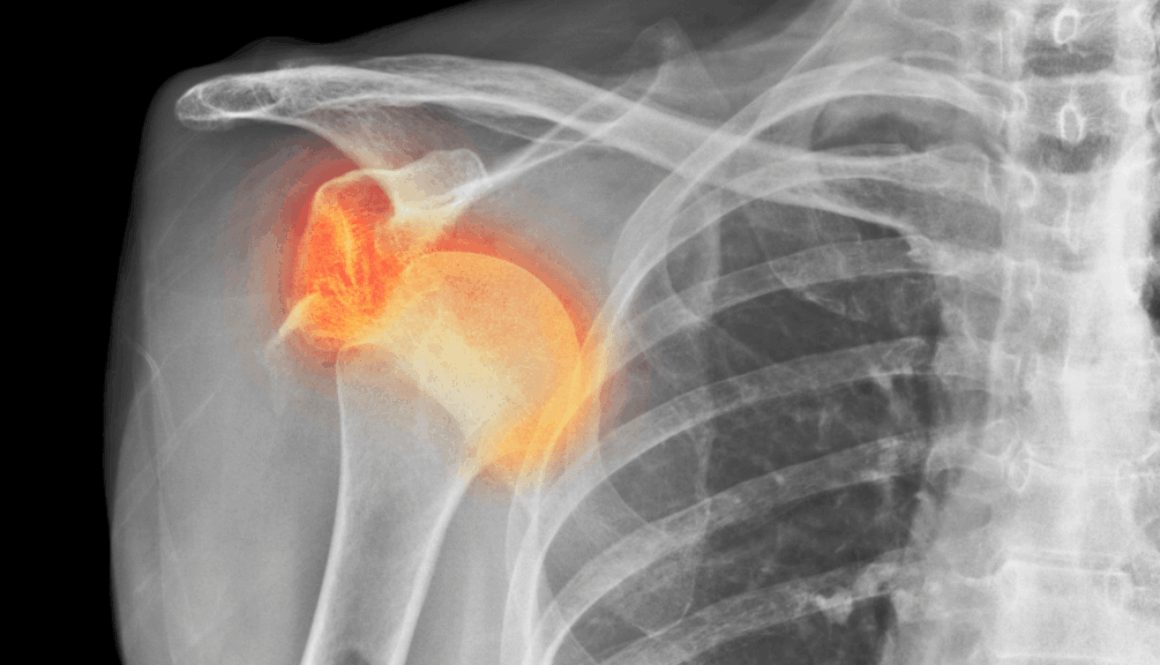

In einigen Fällen können bei einer traumatischen Schulterluxation mehrere Strukturen beschädigt werden. Zunächst kann einmal das Bindegewebe der Kapsel und/oder des Labrums gedehnt werden oder reißen. Zum anderen kann sich eine knöcherne „Bankart-Läsion“ entwickeln, bei der es durch den Aufprall zu einer Fraktur am unteren Ende der Schulterpfanne kommt. Dies geht häufig mit einer „Hill-Sachs-Läsion“ einher, einer Delle in der Schulterkopf selbst. Eine Röntgenaufnahme der Schulter kann dies entweder zeigen oder ausschließen.

Bei einer (traumatischen) Auskuglung ist es wichtig, dass eine Bildgebende Untersuchung durchgeführt wird, um weitere Läsionen und mögliche Brüche auszuschließen.